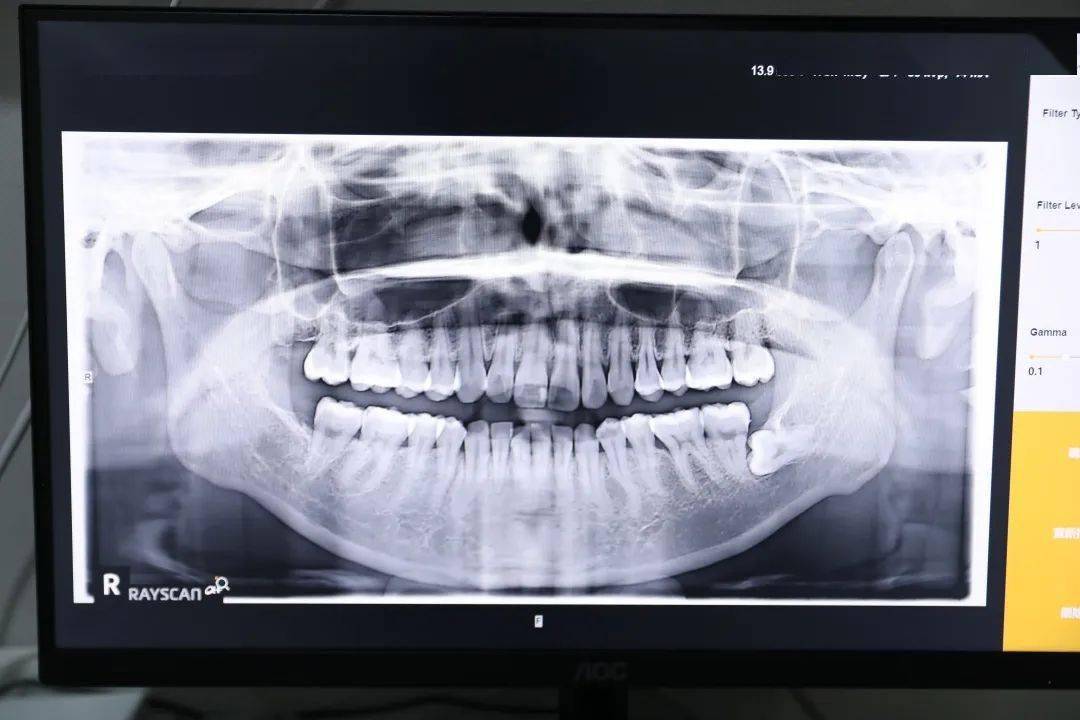

初诊方案ok的话 , 只要付一个900元的定金 , 就可以进行口腔全景扫描 , 侧位扫描还有CT图 , 每一颗牙齿的根部 , 还有伸长走向都记录的清清楚楚 。

文章图片

这就是我的片子哈哈哈!

整体还可以 , 调整之后会更好看